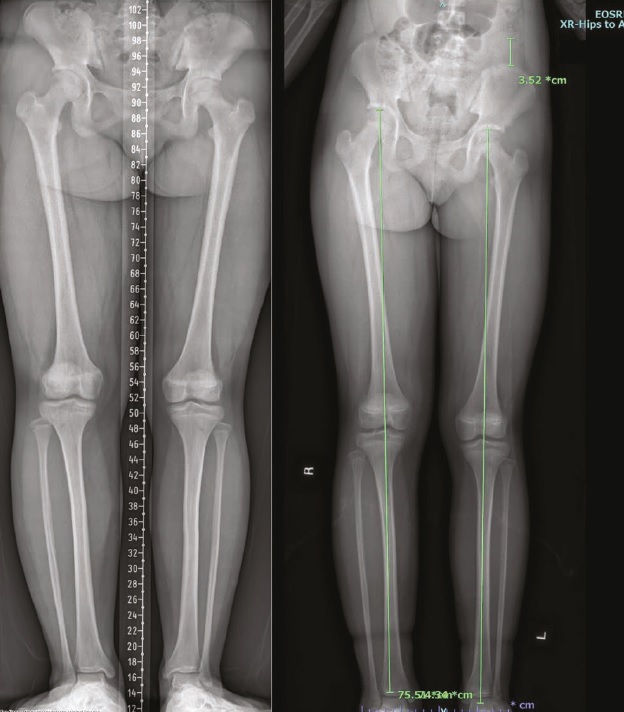

Been lengte verschil

Deze studie keek naar kinderen met een capillaire malformatie (CM) op het been — een geboortevlek die soms ook het weefsel- en botgroei kan beïnvloeden. Het doel was om te onderzoeken hoe vaak deze kinderen een beenlengteverschil (LLD) ontwikkelen en welke factoren dat risico verhogen.

• Van de 1008 kinderen ontwikkelde 14,8% een significant beenlengteverschil van 2 cm of meer.

• Kinderen met een diffuse capillaire malformatie (DCM) hadden het hoogste risico: 44,5% ontwikkelde een groot LLD.

• Tot de leeftijd van 15 jaar is het algemene risico op een groot LLD 31,4%, oplopend tot 66,4% bij kinderen met DCM.